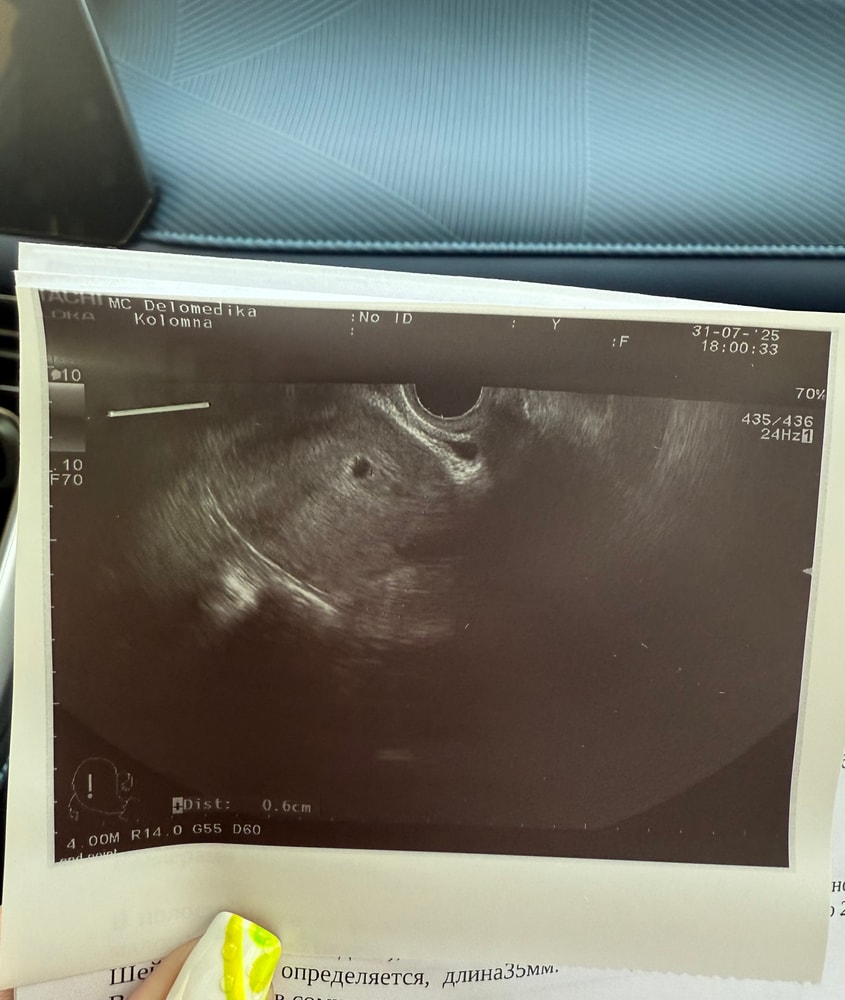

УЗИ какое то пятно

Обследования, узи, анализыДевочки на снимке вижу вверху какое то пятно, что это может быть? Переживаю что что то плохое🫣 это не может быть рубец? Врач вообще ничего не сказала а я сразу не обратила внимания, смотрела только на пя😀